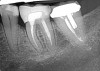

(17.) Case 3 initial radiograph of bridge on Nos. 6 through 9 and crown on No. 10.

Figure 17

(18.) Case 3 initial radiograph of bridge on Nos. 6 through 9 and crown on No. 10.

Figure 18

A 42-year-old man presented with a very loose bridge on Nos. 6 through 9 with periodontally compromised retainers on Nos. 6 and 9 (Figure 17 through Figure 19), and endodontically involved No. 10 with a calcified canal. Teeth Nos. 6, 9, and 10 were extracted, the sockets fully debrided, and pontic soft tissue on Nos. 7 and 8 sculpted to be symmetrical in soft tissue contour with the contralateral lateral incisor and central incisor locations. Implants were secured in position Nos. 6 through 10 (Figure 20) in excess of 45 Ncm, the bone was milled to provide unimpeded seating of temporary abutments, and temporary crowns were fabricated chairside and adjusted to be out of occlusion in centric relation and all excursions. The temporary crowns were cemented after extrusion of excess cement extraorally and the patient was prescribed antibiotics, analgesics, and instructed in postoperative care particular to immediately provisionally restored implants. At 6 months, integration was confirmed (Figure 20 through Figure 23) and after placement of scanning abutments, the implants and soft tissues were scanned. Final crowns were fabricated from the scanned images and were cemented after extrusion of excess cement extraorally (Figure 24 through Figure 26), and oral hygiene procedures were reviewed.